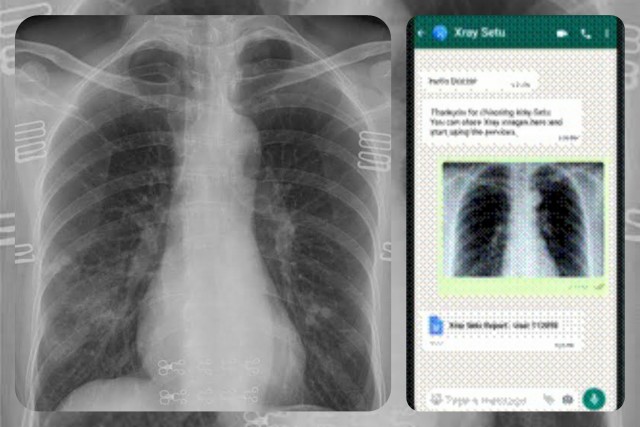

दिल्ली। कृत्रिम बौद्धिकता प्लेटफार्म से व्हॉट्स-एप्प के जरिये कोविड के मामले में शीघ्र कार्रवाई करने की सुविधा मिल गई है। और अब कोविड-19 के खिलाफ फौरन कार्रवाई करने के लिये कृत्रिम बौद्धिकता आधारित प्लेटफार्म का सहारा लिया जायेगा। इसके तहत छाती का एक्स-रे करके उसे डॉक्टरों के पास व्हॉट्स-एप्प के जरिये भेज दिया जायेगा।

डॉक्टर उसे एक्स-रे मशीन पर देख सकते हैं। इस प्रक्रिया का नाम एक्स-रे सेतु रखा गया है और कम रेजोल्यूशन वाली फोटो को मोबाइल के जरिये भेजा जा सकता है। ग्रामीण इलाकों में कोविड की जांच और कार्रवाई के हवाले से इससे आसानी और तेजी से काम हो सकता है। भारत के ग्रामीण इलाकों में कोविड ने कहर बरपा कर रखा है, जिसे मद्देनजर रखते हुये, तेज गति से जांच करना, यह जानना कि किस मरीज का किन-किन लोगों से संपर्क हुआ और कंटेनमेंट जोन बनाना बहुत जरूरी हो गया है।

बेंगलुरू स्थित हेल्थ-टेक स्टार्ट-अप निरामय और भारतीय विज्ञान संस्थान ने विज्ञान और प्रौद्योगिकी विभाग के साथ मिलकर एक्स-रे सेतु का विकास किया है। इसे कोविड पॉजीटिव मरीजों की पहचान करने और व्हाट्स-एप्प के जरिये उनकी छाती के एक्स-रे को कम रेजूल्युशन पर डॉक्टर तक भेजने की सुविधा के लिये तैयार किया गया है। इसमें प्रभावित इलाकों का विश्लेषण और उसे रंगों के जरिये मानचित्र (हीटमैप) द्वारा समीक्षा भी की जायेगी। यह समीक्षा डॉक्टरों के लिये उपलब्ध रहेगी, ताकि वे आसानी से हालात के बारे में जान सकें।

इसके जरिये भारत के दूर-दराज इलाकों से 1200 से अधिक रिपोर्ट मिली हैं। स्वास्थ्य की जांच करने के लिये किसी भी डॉक्टर को सिर्फ www.xraysetu.com पर जाकर ‘ट्राई दी फ्री एक्स-रे सेतु बीटा’ बटन को क्लिक करना है। उसके बाद यह प्लेटफार्म उन्हें सीधे दूसरे पेज पर ले जायेगा, जहां उक्त डॉक्टर वेब या स्मार्टफोन एप्लीकेशन के जरिये व्हॉट्स-एप्प आधारित चैट-बॉट से जुड़ जायेंगे।

इसके अलावा डॉक्टर लोग एक्स-रे सेतु सेवा शुरू करने के लिये +91 8046163838 पर व्हॉट्स-एप्प संदेश भेज सकते हैं। उन्हें बस मरीज के एक्स-रे इमेज को क्लिक करना है और चंद मिनटों में ही सम्बंधित तस्वीरें और निदान की पूरी व्याख्या वाले दो पेज निकल आयेंगे। कोविड-19 का किसी विशेष स्थान पर ज्यादा प्रभाव डालने की संभावना को ध्यान में रखते हुये, रिपोर्ट में डॉक्टरों की सुविधा के लिये हीट-मैप का भी उल्लेख रहेगा। इंग्लैंड के नेशनल इंस्टीट्यूट ऑफ हेल्थ ने 1,25,000 से अधिक एक्स-रे तस्वीरों को इस प्रक्रिया से जांचा है। इसी तरह एक्स-रे सेतु से एक हजार से अधिक भारतीय कोविड मरीजों की जानकारी हासिल की गई है। इस प्रक्रिया के शानदार नतीजे निकले हैं। आंकड़ों की संवेदनशीलता 98.86 प्रतिशत और सटीकता 74.74 प्रतिशत है। आर्टपार्क के संस्थापक और सीईओ श्री उमाकांत सोनी का कहना है, “हमें 1.36 अरब लोगों की जरूरतों को ध्यान में रखते हुये प्रौद्योगिकी का विकास करना है।